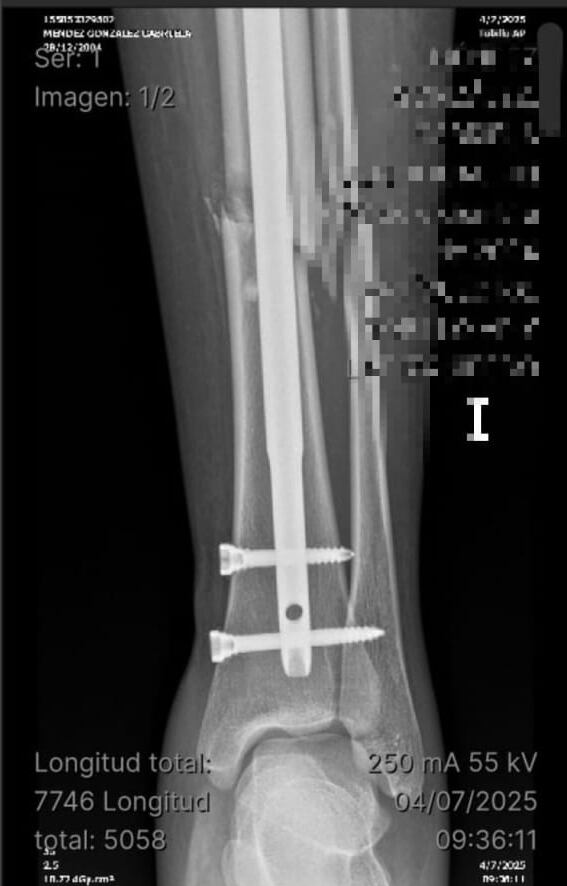

Producto del accidente, Gabriela sufrió una fractura de tibia y peroné expuesta grado dos en su pierna izquierda. Días después del accidente, pasó por la sala de cirugía y le colocaron un clavo bloqueado (una especie de varilla que se coloca para estabilizar el hueso); sin embargo, a la fecha sigue con molestias, a diario tiene calentura y no puede trabajar.